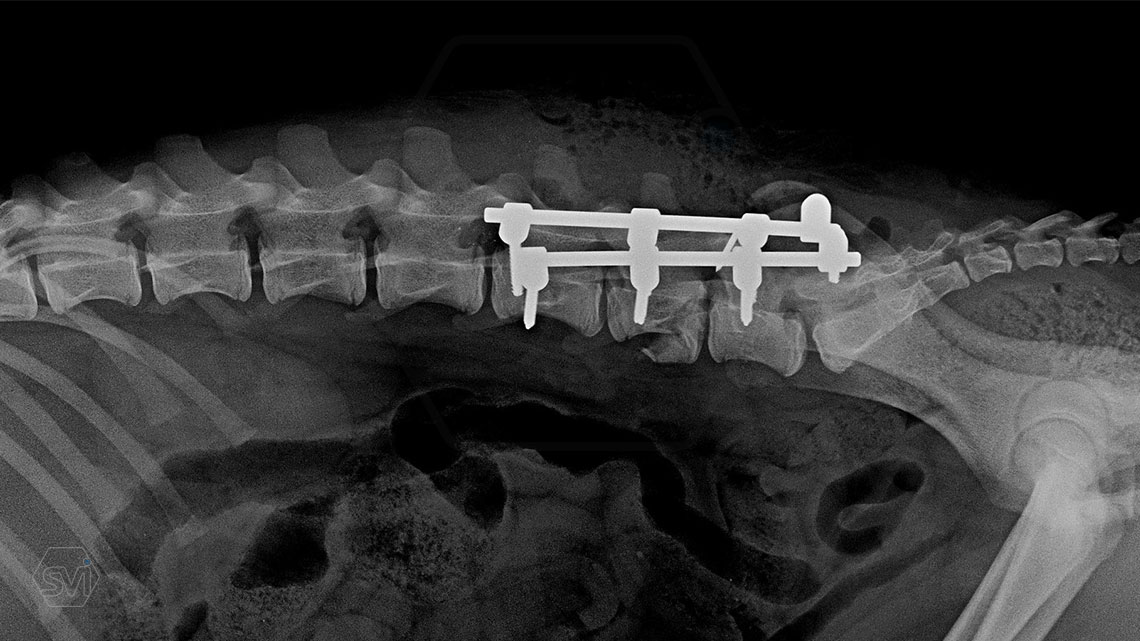

L6 vertebral body fracture fixation with 2.7-mm SOP-LC system